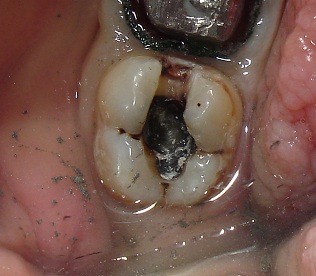

Это исходная ситуация перед началом работы с данным зубом.

На вид зуб целый, пусть Вас не смущает цвет пломбы -1 - это амальгама (Вам известна она под названием -серебряная пломба), 2-пломба из композитного материала.

Вот, что мы видим, убрав пломбы с зуба.

Обширный кариозный процесс.

Кстати, вторая пломба на этот зуб была поставлена 3 года назад, уже имея кариес под первой пломбой (как оказалось после того, как были убраны старые пломбы).

В доказательство, кариозные процессы разделены здоровой тканью.